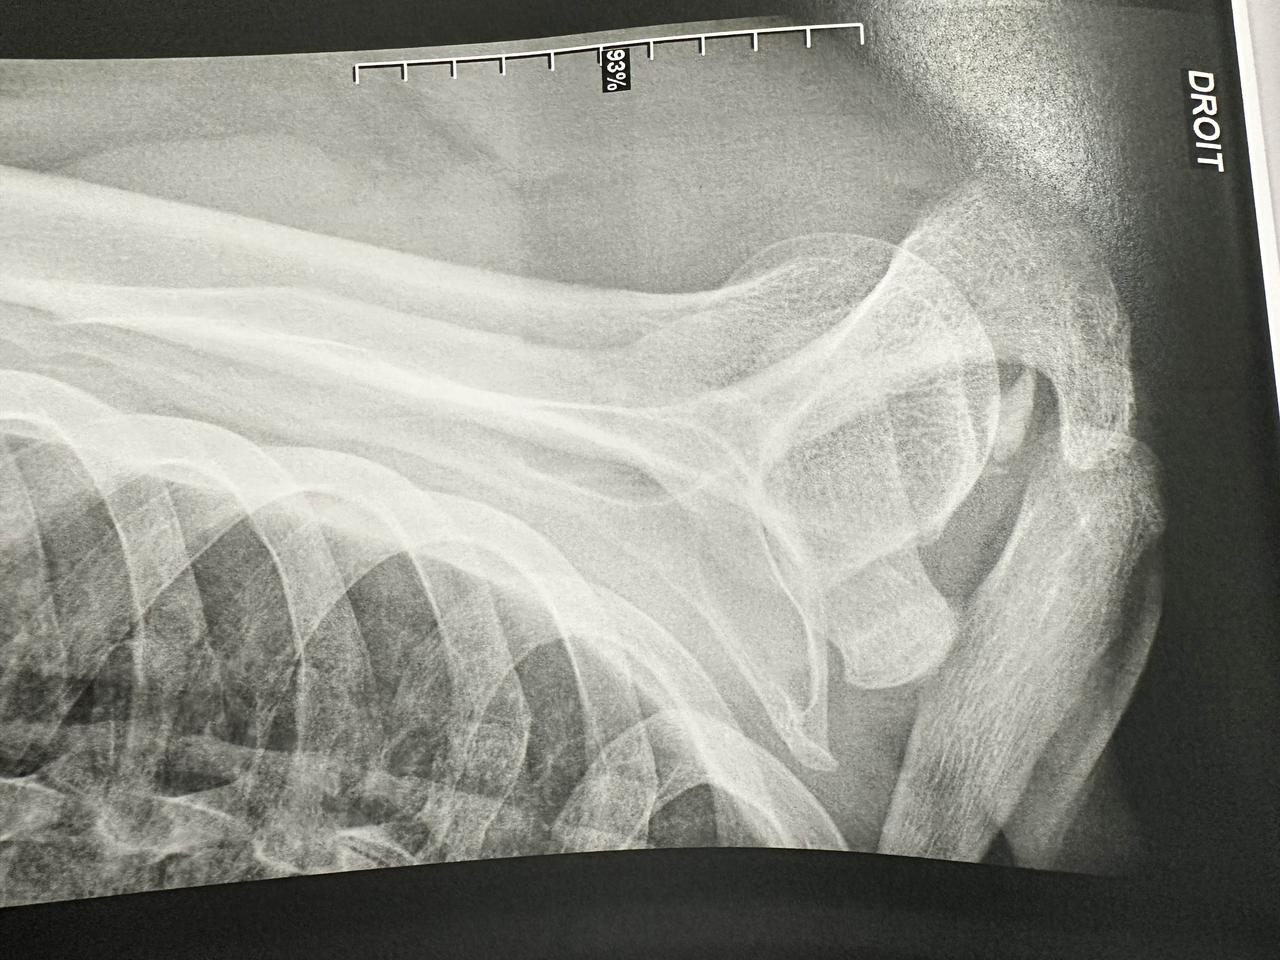

在法国看病的奇怪经历。 谢谢好多网友粉丝的关心,肩膀骨头没有大问题。 真的年纪大了什么都要注意,过马路一个趔趄肩膀都能摔的这么严重,第二天去了医院,拍了片子,没有骨折但可能有些错位。 我这次旅行是买了一年的旅游保险的,一年700块,任何小病和意外都在保险范围内,包括感冒发烧去医院治疗都报销的。 然后法国护士大夫基本是说法语的,我这次正好随身带了翻译机,比手机翻译确实方便多了。很多都是我在听同声传译,知道他们的意思。 不过最后我没他懂为什么没让我付款,治疗完大夫给我了两张诊断书就说我可以走了。我说我要付款吗,去哪里付款,他一愣,就叫了个黑人护士,带着我走了好几个楼,我估计是从急诊楼走到了门诊楼吧,进了个小屋里面有两个窗口,把我的单子递上去,大夫敲击了一下电脑,和旁边的人说了句什么,说今天不能交费,另一个人就说不用交费,让我可以走了。我很奇怪,也不好意思再问,一脸茫然的就走了。 这应该不是对外国人的福利吧?他们除了复印了我的护照没要其他东西,以后不会因为我没交费,说我逃避医疗费禁止给我签证和入境吧。